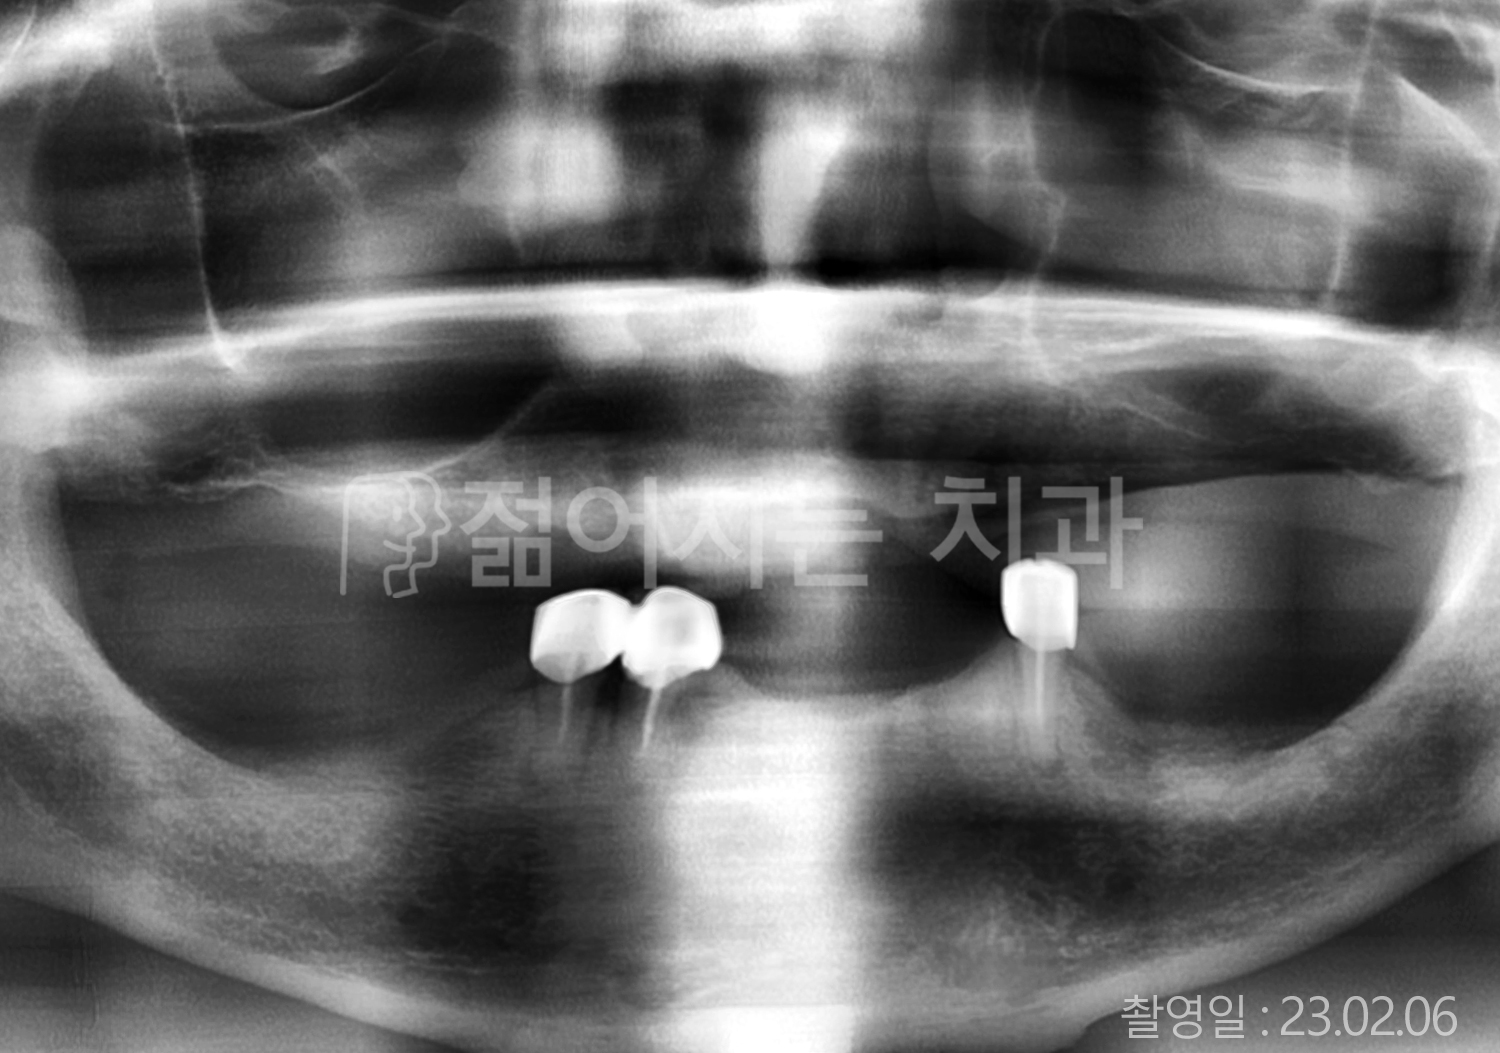

• 70대 고혈압, 당뇨 전체치아 10개 이상 임플란트

• 50대 고혈압, 당뇨 전체치아 10개 이상 임플란트

• 60대 고혈압, 당뇨 전체치아 10개 이상 임플란트

• 50대 전체치아 10개 이상 임플란트

• 70대 당뇨 전체치아 10개 이상 임플란트

• 80대 전체치아 10개 이상 임플란트

• 40대 전체치아 10개 이상 임플란트

• 60대 고협압, 고지혈증 전체치아 10개 이상 임플란트

• 60대 전체치아 10개 이상 임플란트